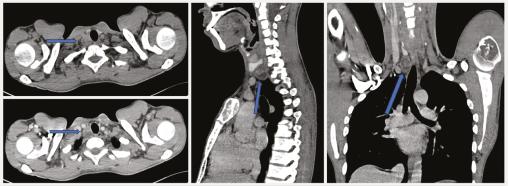

Un scanner cervico-thoraco-abdomino-pelvien (CTAP) réalisé par la suite montre la présence d’une formation rétrothyroïdienne droite, bien limitée, hypodense, se rehaussant après injection de produit de contraste, de 20 mm de grand axe faisant évoquer un adénome parathyroïdien (fig. 1 ). Un deuxième CTAP met en évidence de multiples lésions ostéolytiques du squelette axial et périphérique soufflant et rompant la corticale osseuse par endroits et se rehaussant après injection de produit de contraste, correspondant à des tumeurs brunes (fig. 2 ).

Un scanner cervico-thoraco-abdomino-pelvien (CTAP) réalisé par la suite montre la présence d’une formation rétrothyroïdienne droite, bien limitée, hypodense, se rehaussant après injection de produit de contraste, de 20 mm de grand axe faisant évoquer un adénome parathyroïdien (